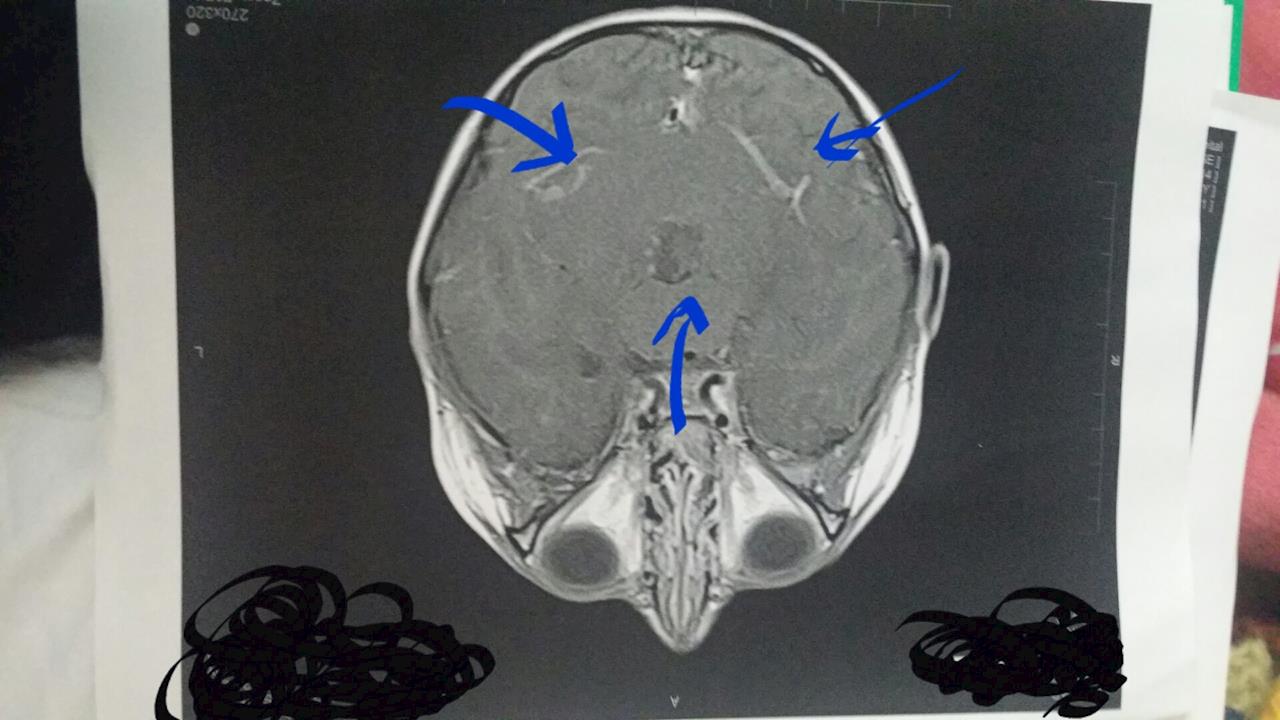

Tobi's Mri and Lumber Puncture All went well.

It is part of the pre testing for his treatment plan.

L.P is to Make sure there's no bad cells floating down the spine & MRi is to check there's no visible bits left.

Hopefully we will find out on Monday if his ventricles have reduced in size some more since the last one...

MRI was this morning.

Just spoke to registra.

Scan looks good. From what we can see the tumor is gone - but until we get biopsy results of what type the tumour is, we won't know about any treatment /microscopic bits that maybe left which may regrow, that we can't see on scan.

His 1st and second ventricles are still larger than they're meant to be but they are smaller than before surgery. It does take a while for them to go back to a regular size... there are 2 small pockets of air in the 1st & 2nd ventricles from the drain (which is normal) but the body will rid that itself.

13th March Tobi had his major surgery to remove the tumour in the cerebellar.

It was 56mm x 36mm x 29mm in size.

Surgery took just over 5 hours all up.